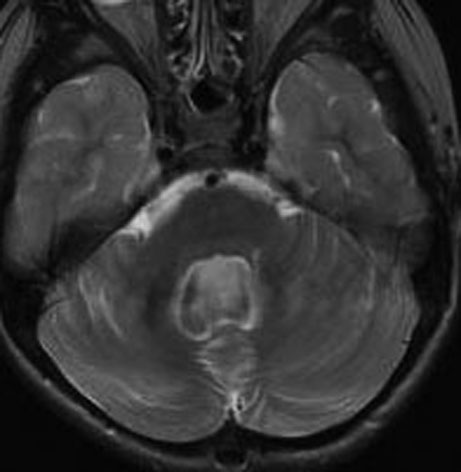

12歳の少女の小脳虫部と右半球深部白質の間にできた毛様細胞性星細胞腫 pilocytic astrocytoma です。軽い体幹失調がありました。のう胞壁の大部分には腫瘍はありませんが,一部に腫瘍壁があります。必ずしも境界は明瞭ではなく,小脳虫部の上内側面に広範囲に接着しています。年長児の毛様細胞性星細胞腫は,Rosental fiber, eosinophilic granular bodyが多く見られ,硬く,小脳脳組織に食い込み,簡単に剥離摘出できるものではありません。脳組織と切開切断するように切り落とさなければ全摘できないものです。

右側は手術直後のFLAIR像です。小児ですから大きなのう胞はすぐに潰れて小脳がもどります。白質損傷もなく腫瘍は摘出できています。